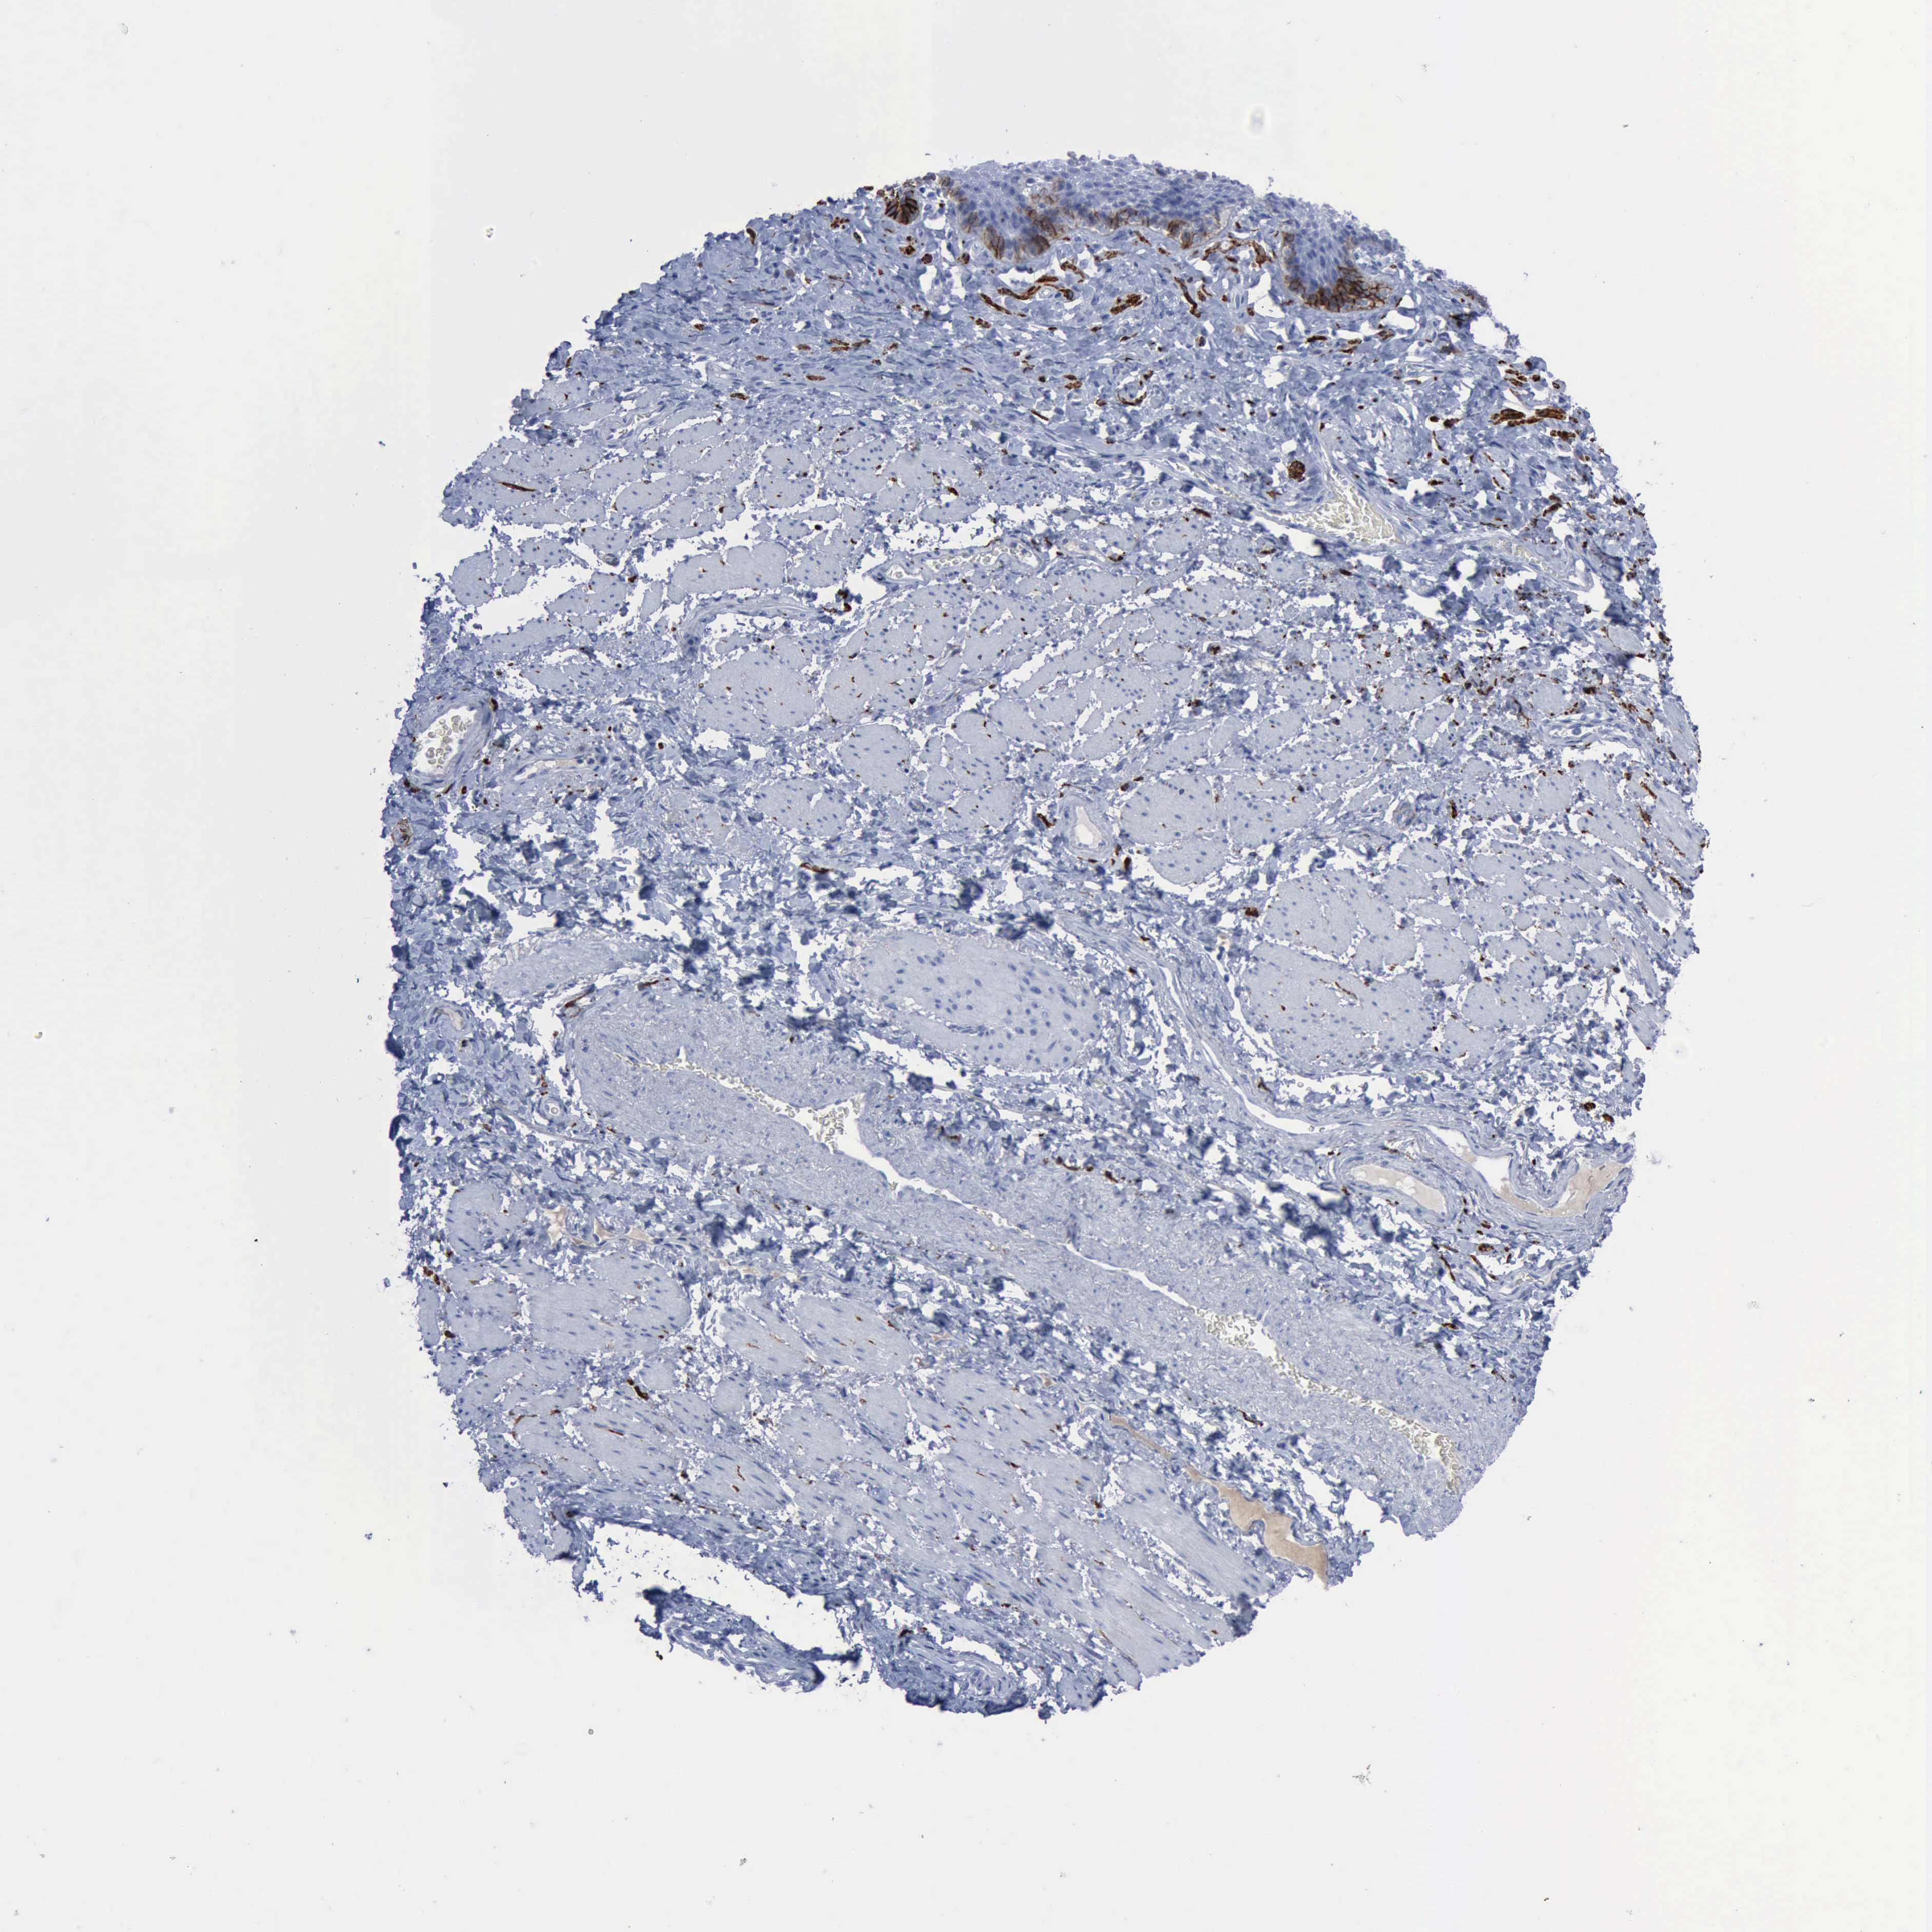

ESOPHAGUS - Antibody stainingi

Antibody staining in the annotated cell types in the current human tissue is reported as not detected, low, medium, or high, based on conventional immunohistochemistry profiling in selected tissues. This score is based on the combination of the staining intensity and fraction of stained cells.

Each image is clickable and will lead to virtual microscopy that enables deeper exploration of all samples and also displays staining intensity scores, fraction scores and subcellular localization as well as patient and tissue information for each sample.

Antibody HPA004765Antibody CAB000143Antibody CAB001995

Squamous epithelial cells MediumMediumLow